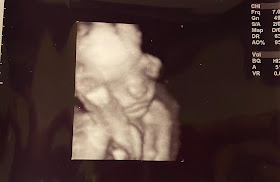

Baby pictures!!

I actually LEFT THE HOUSE for my 20-week ultrasound yesterday!

And while I HATED going to a medical facility, it was so great to see her swimming around in there.

She looks perfect and is measuring exactly on track for an August 23 due date. There was a tiny concern with the thickness of my placenta that could lead to extra monitoring next trimester or could just be normal and the shape of my placenta (which looked perfect by every other measure), but I go back in about 5 weeks to have another peek and also to drink that gross glucose drink and do a CBC. I am glad to condense all of my labs to a dingle visit, and I had a tele-medicine appointment today, meaning I don't have to go back to the midwife clinic until 5/18.

(She was curled up in the teeniest little ball, which is why there's a knee in her face in the 3D pics and why her spine shot looks like a fish)